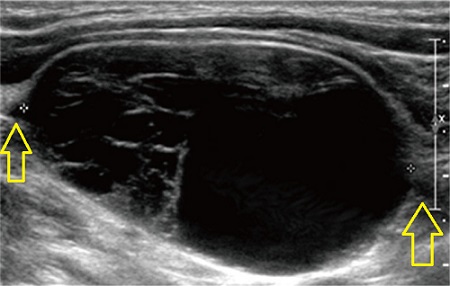

- 充実性、均一エコー型(solid pattern);エラストグラフィーでは硬い

- 不均一エコー型(multiple microcystic pattern)

- 辺縁増強を伴う嚢胞型(cystic pattern)

があります(耳鼻34:677 ~683 ,1988.)。

頚部神経鞘腫(schwannoma)は、穿刺細胞診では、紡錘形細胞よりさらに細長い「うなぎ様核(eel-like nuclei)」を持つ細胞です(Cancer Cytopathol. 2015 Mar;123(3):171-9.)。しかし、十分な組織片が得られない事も多く、術前の診断が付くのは約半数です。組織診ができれば、紡錘形細胞が錯綜する構造で、免疫染色ではS-100陽性です。